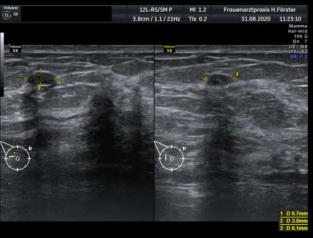

Gynäkologische Grundversorgung Frauenärztliche Krebsfrüherkennungsuntersuchung Nachsorge und supportive Therapie bei bösartigen gynäkologischen Tumoren Impfungen Brustultraschall Ultraschalluntersuchung der weiblichen Genitalorgane Psychosomatische Grundversorgung Chlamydienscreening FOB-Test (früher Hämoccult) Kontrazeption Geburtshilfliche Grundversorgung Geburtshilflicher Basisultraschall Erweiterter Basisultraschall (Organscreening) zw, 18-22.SSW Doppler/Duplexsonografie des fetomaternalen Gefäßsystems Infektionsscreening in der Schwangerschaft CTG (Kardiotokographie) Gynäkologische Grundversorgung Dies umfasst die Abklärung und Behandlung gynäkologischer Erkrankungen. Eine große Rolle dabei spielt das ärztliche Gespräch, ergänzt bei Notwendigkeit durch die gynäkologische Untersuchung oder Untersuchung der weiblichen Brust. In vielen Fällen werden noch Zusatzuntersuchungen durchgeführt (z.B. Ultraschalluntersuchungen, Abstrichentnahmen, Blutentnahmen) oder weiterführende Untersuchungen veranlasst (z.B. Röntgenuntersuchungen). >> zurück << Frauenärztliche Krebsfrüherkennungsuntersuchung Die Krebsfrüherkennungsuntersuchung der Frau ist wahrscheinlich die bekannteste Leistung unseres Fachgebietes. Ab dem Alter von 20Jahren hat jede Frau ein Anrecht auf diese jährliche Untersuchung. Dabei werden der Unterleib der Frau und ab dem Alter von 30Jahren auch die Brüste der Frau systematisch klinisch untersucht. Zusätzlich erfolgte seit vielen Jahren ein Pap-Abstrich vom Gebärmutterhals. So konnten Zellveränderungen meist rechtzeitig erkannt und behandelt werden und es wurde erreicht, daß das früher sehr häufige Zervixkarzinom (Gebärmutterhalskrebs) heute nur noch selten auftritt. Um die Qualität weiter zu verbessern erfolgte 2020 eine Neuordnung des Screenings mit Überarbeitung der Abstrichintervalle und Hinzunahme von HPV-Abstrichen ab 35 als Kassenleistung. >> zurück << Nachsorge und supportive Therapie bei bösartigen gynäkologischen Tumoren Nach Abschluss und oft auch wärend der Primärbehandlung können Probleme auftreten. Es macht also Sinn, sich in regelmäßigen Abständen zu treffen, um das weitere Vorgehen zu planen, eventuell Zusatzuntersuchungen zu veranlassen oder zusätzlich wegen der Beschwerden zu behandeln. Die Nachsorgeuntersuchungen finden anfangs engmaschig statt, später werden die Intervalle länger. >> zurück << Impfungen In Zeiten der Globalisierung, zunehmender Reisefreudigkeit und Zuwanderung werden wir wieder mit Infektionserregern konfrontiert, die wir schon als besiegt geglaubt hatten. Gleichzeitig werden wir immer älter und unser Immunsystem dabei nicht besser. Es reicht nicht, mal eben alle 10Jahre Tetanus zu impfen. Sind Sie geschützt? Wissen Sie was empfohlen ist? Bringen Sie den Impfausweis (auch den alten!!) mit. Wir prüfen Ihren Impfstatus, geben Ihnen Empfehlungen. Die gängigsten Impfstoffe haben wir auch vorrätig und können Sie impfen. >> zurück << Brustultraschall Die Ultraschalluntersuchung der Brust (Mammasonografie) kommt zur Abklärung von krankhaften Veränderungen zur Anwendung oder als Zusatzuntersuchung in der Früherkennung von Brustkrebs bei sehr dichtem Gewebe oder familiärer Vorbelastung. Sie ersetzt nicht das organisierte Mammographiescreening und ist nicht Bestandteil der normalen Krebsfrüherkennung. Es handelt sich um eine schmerzfreie Untersuchung ohne Strahlenbelastung. Die Mammasonografie  ist auch als Wunschleistung (IGeL) möglich. >> zurück << Ultraschalluntersuchung der weiblichen Genitalorgane Die Ultraschalluntersuchung der weiblichen Genitalorgane kommt zur Abklärung von krankhaften Veränderungen des weiblichen Genitales zur Anwendung. Dabei werden mit einer hochfrequenten Vaginalsonde die Organstrukturen im kleinen Becken untersucht. Die Untersuchung ist bei schlanken und sehr jungen Frauen auch vom Bauch aus möglich, die Genauigkeit ist dabei technisch bedingt aber schlechter.  Sie ist nicht Bestandteil der normalen Krebsfrüherkennung. Auch diese Untersuchung ist als Wunschleistung (IGeL) möglich. >> zurück << Psychosomatische Grundversorgung Jede Erkrankung belastet die Seele. Eine seelische Belastung macht den Körper krank. Jeder weiß das. Die Zusammenhänge zwischen dem kranken Körper und der kranken Seele beschreibt die Psychosomatik. Ein "Gordischer Knoten", der nur schwer zu zerschlagen ist, oft ein langer Weg. Ziel ist es, diese Zusammenhänge zu erkennen und den Betroffenen zu helfen ihren Weg zu finden. Oft ist die Zusammenarbeit mit einer Psychologin/ Psychologen nötig. Wichtig ist die Hilfe bei den ersten Schritten. Laufen müssen Sie selbst. >> zurück << Chlamydienscreening Das Bakterium Chlamydia trachomatis kann beim Sex übertragen werden und zu Entzündungen und sogar zur Unfruchtbarkeit führen. Deshalb bezahlen die Krankenkassen bis zum vollendeten 25.Lebensjahr allen sexuell aktiven Frauen einen Suchtest auf Chlamydien. Sie müssen lediglich eine Urinprobe abgeben. Auch in jeder Schwangerschaft wird nach Chlamydien gefahndet. Da Frauen im Normalfall auch im Alter über 25Jahren sexuell aktiv sind und noch schwanger werden wollen bieten wir die Testung auch als Wunschleistung (IGeL) an. Der Test wird dann aus einem Abstrich aus dem Muttermund entnommen, dies kann bei der Krebsfrüherkennung mit gemacht werden. >> zurück << FOB-Test (früher Hämoccult) Im Alter von 50 bis 54Jahren bezahlen die Krankenkassen allen versicherten Frauen einen Stuhltest zur Früherkennung von Darmkrebs oder seiner Vorstufen. Mit 55Jahren können Sie sich entscheiden zwischen zwei Darmspiegelungen im Abstand von 10Jahren oder der Fortführung der Stuhlteste alle 2Jahre. Natürlich kann man Stuhlteste auch zwischen den Darmspiegelungen machen lassen oder auch bei Frauen jünger als 50. Wir bieten dies als Wunschleistung (IGeL) unseren Patienten an. >> zurück << Kontrazeption Ein selbstbestimmtes Leben als Frau ist bei uns in Deutschland eine Selbstverständigkeit. Das war nicht immer so.  Kinder-Küche-Kirche hieß es früher, damals, in der guten alten Zeit. Das ist zum Glück vorbei. Und begonnen hat alles mit der Pille. Frauen konnten endlich über ihren Körper selbst bestimmen, ohne Angst ihre Liebe leben.  Aber die Pille ist nicht alles. Viele Märchen sind im Umlauf, Fehlinformation. Aber auch fehlendes Wissen zu Risiken.  Wir beraten Sie gern. >> zurück << Geburtshilfliche Grundversorgung In der Schwangerenberatung werden die werdenden Muttis gemäß den geltenden Mutterschaftsrichtlinien vom Anfang der Schwangerschaft bis zur Abschlussuntersuchung (6-8 Wochen nach der Geburt) betreut. >> zurück << Geburtshilflicher Basisultraschall Nach Vorgabe der Mutterschaftsrichtlinie sind sind in der Schwangerschaft 3 Ultraschalluntersuchungen vorgesehen. Diese finden in der 8.-12. SWW, in der 18,- 22. SSW und in der 28.-32.SSW statt. Dabei werden der Zustand des Embryos/ Feten, des Fruchtwassers und der Plazenta beurteilt. >> zurück << Erweiterter Basisultraschall (Organscreening) zw. 18-22.SSW Bei der zweiten Ultraschalluntersuchung (zw.18.-22. SSW) erfolgt ein erweitertes Screening mit Beurteilung der Organstrukturen des Kindes. Diese Untersuchung ist Kassenleistung, kann aber bei Wunsch auch Abgewählt werden, dann wird nur der Basisultraschall durchgeführt. >> zurück << Doppler/Duplexsonografie des fetomaternalen Gefäßsystems Bei Aüffälligkeiten im Schwangerschaftsverlauf oder auch bei bestimmten Vorerkrankungen oder Erkrankungen in einer früheren Schwangerschaft kann es notwendig sein die Durchblutung des Mutterkuchens und der Gefäße des Kindes zu Untersuchen. Hier kommt das Dopplerverfahren als Erweiterung des normalen geburtshilflichen Ultraschalls zum Einsatz. Dies erlaubt eine schnelle Zustandsbeurteilung des Kindes pepaart mit einer zeitlich begrenzten Vorhersage über die weitere wahrscheinliche Entwicklung. Bei entsprechender Indikation ist diese Untersuchung als Kassenleistung abrechenbar. >> zurück << Infektionsscreening in der Schwangerschaft Die Suche nach Krankheitserregern im Krankheitsfall ist Kassenleistung. Routinemäßig prüfen wir Ihren Schutz vor Röteln und Windpocken , in jeder Schwangerschaft erfolgt ein Test auf Chlamydien. Zusätzlich empfehlen wir jeder Schwangeren einen Test auf eine Besiedelung mit Gruppe-B-Streptokokken vor der Geburt. Diese Streptokokken können zu schweren Atemwegsinfektionen des Neugeborenen führen. Eine vorbeugende Behandlung bei positivem Test kann dann unter der Geburt erfolgen. Bei Wunsch kann auch ein erweitertes Erregerscreening über unser Labor erfolgen (Wunschleistung). Eine wichtige Rolle spielt auch die Kontrolle auf einen Schutz gegen eine Toxoplasmoseinfektion. Bei fehlendem Schutz empfielt sich die regelmäßige Testung aus dem Blut auf eine frische Infektion. Auch dies ist eine Privatleistung, wird aber von den meisten Kassen erstattet. Eine nicht erkannte und somit nicht behandelte Erstinfektion in der Schwangerschaft kann zu schweren Schäden beim Kind führen. >> zurück << CTG Ab etwa der 30.Schwangerschaftswoche können wir bei Notwendigkeit im Ramen der Schwangerschaftsvorsorge die kindlichen Herztöne (Kardiographie) und simultan dazu die die Spannung der mütterlichen Bauchdecke (Wehenschreiber, Tokographie) graphisch darstellen. Das nennt man zusammen Kardiotokographie oder kurz einfach CTG. Die Auswertung des CTG‘s erfolgt nach dem Fisher-Score (Punkte-System) sowie nach qualitativen Kriterien und erlaubt uns eine gute Zustandsbeurteilung des Kindes in den späteren Schwangerschaftswochen. >> zurück <<